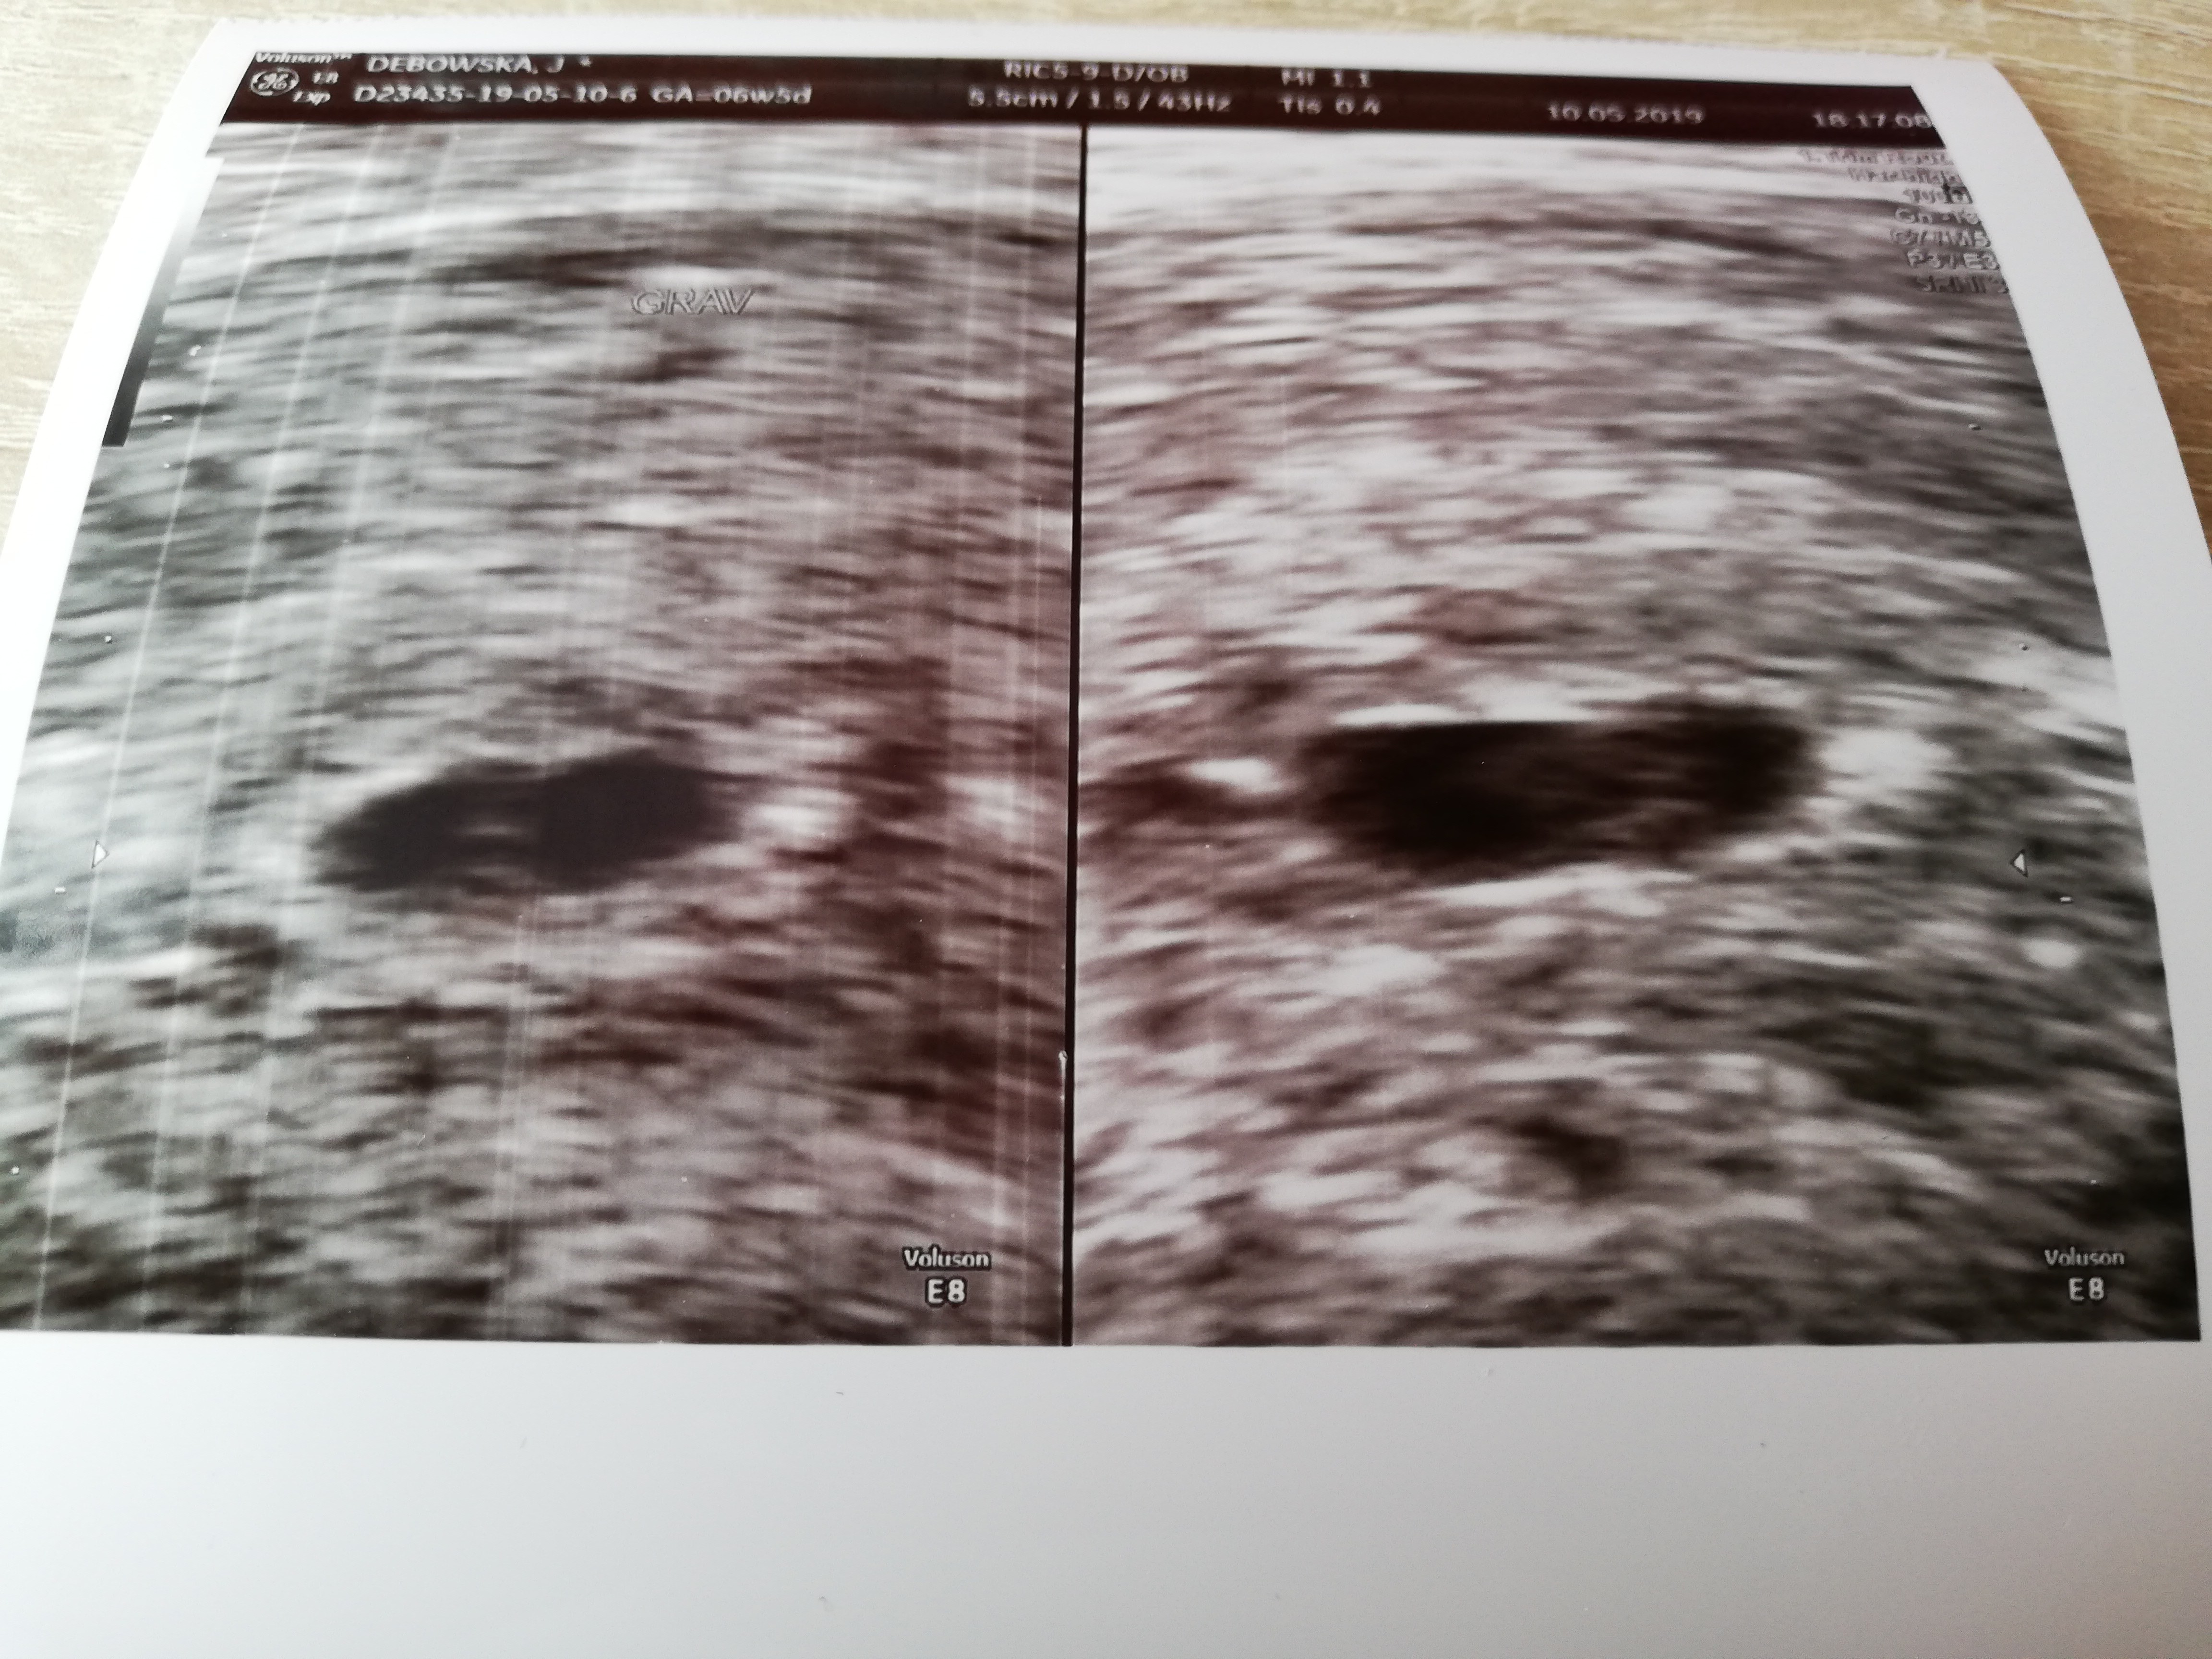

Ja dostałam się jednak wczoraj na wizytę u mnie do mojego lekarza, tą w klinice która miała być dzisiaj odmówiłam bo nie miałabym aktualnego wyniku bety, no więc ogólnie nie jest za kolorowo, jest pęcherzyk ciążowy i żółtkowy, jakiś tam zalążek zarodka doktor mówi że można by się dopatrzeć, ale pęcherzyk ma dziwny kształt taki płaski i to go najbardziej zmartwiło, a poza tym wyszło mu z USG że ciąża ma 5 tygodni z kawałkiem, czyli tydzień mniej niż ma faktycznie. W czwartek mam kolejne USG u niego i zobaczymy czy się coś ruszy...

Ja dostałam się jednak wczoraj na wizytę u mnie do mojego lekarza, tą w klinice która miała być dzisiaj odmówiłam bo nie miałabym aktualnego wyniku bety, no więc ogólnie nie jest za kolorowo, jest pęcherzyk ciążowy i żółtkowy, jakiś tam zalążek zarodka doktor mówi że można by się dopatrzeć, ale pęcherzyk ma dziwny kształt taki płaski i to go najbardziej zmartwiło, a poza tym wyszło mu z USG że ciąża ma 5 tygodni z kawałkiem, czyli tydzień mniej niż ma faktycznie. W czwartek mam kolejne USG u niego i zobaczymy czy się coś ruszy...Zobacz załącznik 971330